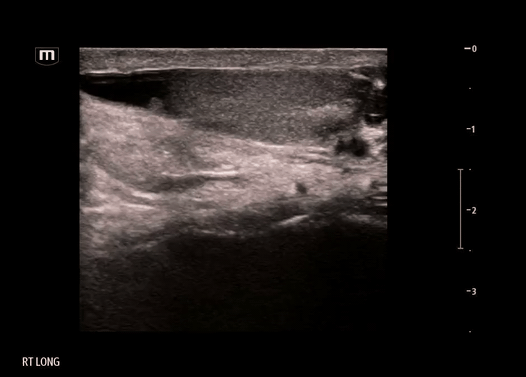

Ultrasound:

Ultrasound was performed on the R scrotum

Findings on our bedside ultrasound:

• The structure is anechoic - fluid-filled, appears to be simple fluid

• The structure has no peristalsis, and there is a lack of typical bowel wall findings - probably not bowel or inguinal hernia

• The structure does not seem to be within the tunica vaginalis - not a hydrocele, where the simple fluid collection would be seen surrounding the testicle itself